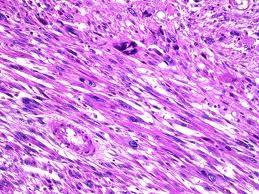

首先,要强调的是,恶变是一个病理诊断,一个外科医生,在将切除的标本送病理检查之前,有的时候是很难鉴别良恶性的。所以,恶变是一个子宫肌瘤的病理诊断。

在以前的教材中,写子宫肌瘤肉瘤变的发生率在0.5%,但是已经找不到来源了,根据我的临床经验,比例可能是要比这个更低。根据美国的人群统计资料,子宫肉瘤在人群发生率为17.1/100万,而对比子宫肌瘤100,000/100万(按照10%的比例)来算的话,那么子宫肌瘤和子宫肉瘤在人群中的比例就差不多在6000:1。也就是说这是一个罕见现象。